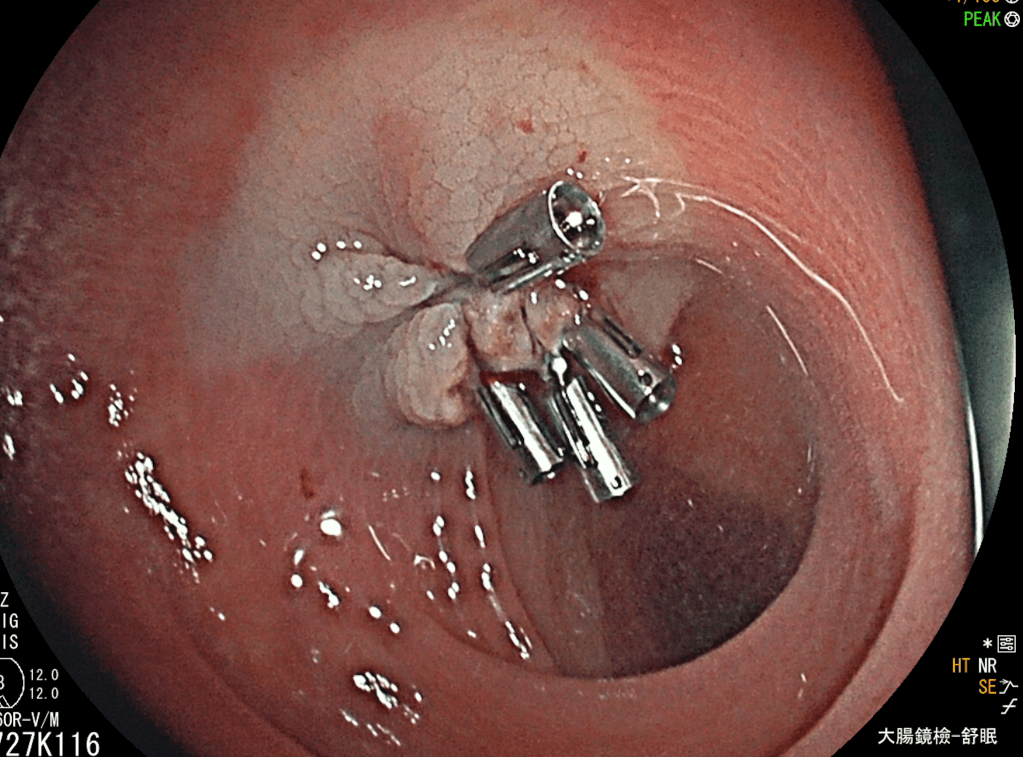

以息肉的大小來,有些診所大腸鏡連小息肉都只看不切,我們是連巨大息肉(>2cm)都處理:

看完上述照片,應該沒人敢說開業醫low吧!而且內視鏡的畫質很棒,這是我來基層快樂的原因,用先進的儀器,發揮過去的所學來服務患者,成就自己。